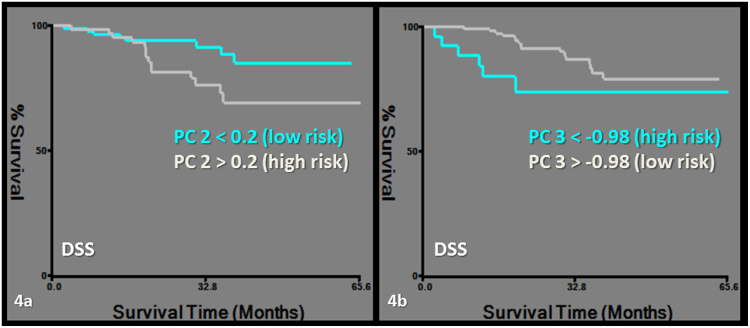

DSS was predicted by PC2, which was exclusively based on CT-derived first order and morphological features, namely the asymmetry group. The same first order features were also clustered in PC1 and PC2 (Tables 2, 3, 4, Fig. 4). RC was predicted by PC4, which is described above (Tables 2, 3, 4, Fig. 5).

Figure 4.

Kaplan-Meier survival curves for disease specific survival (DSS). Subgroups of low and high risk were determined by a cut-off value of 0.2 for PC2 (logrank chi-square: 4.08, p = 0.04) (a) and −0.98 for PC3 (logrank chi-square: 4.21, p = 0.04) (b).